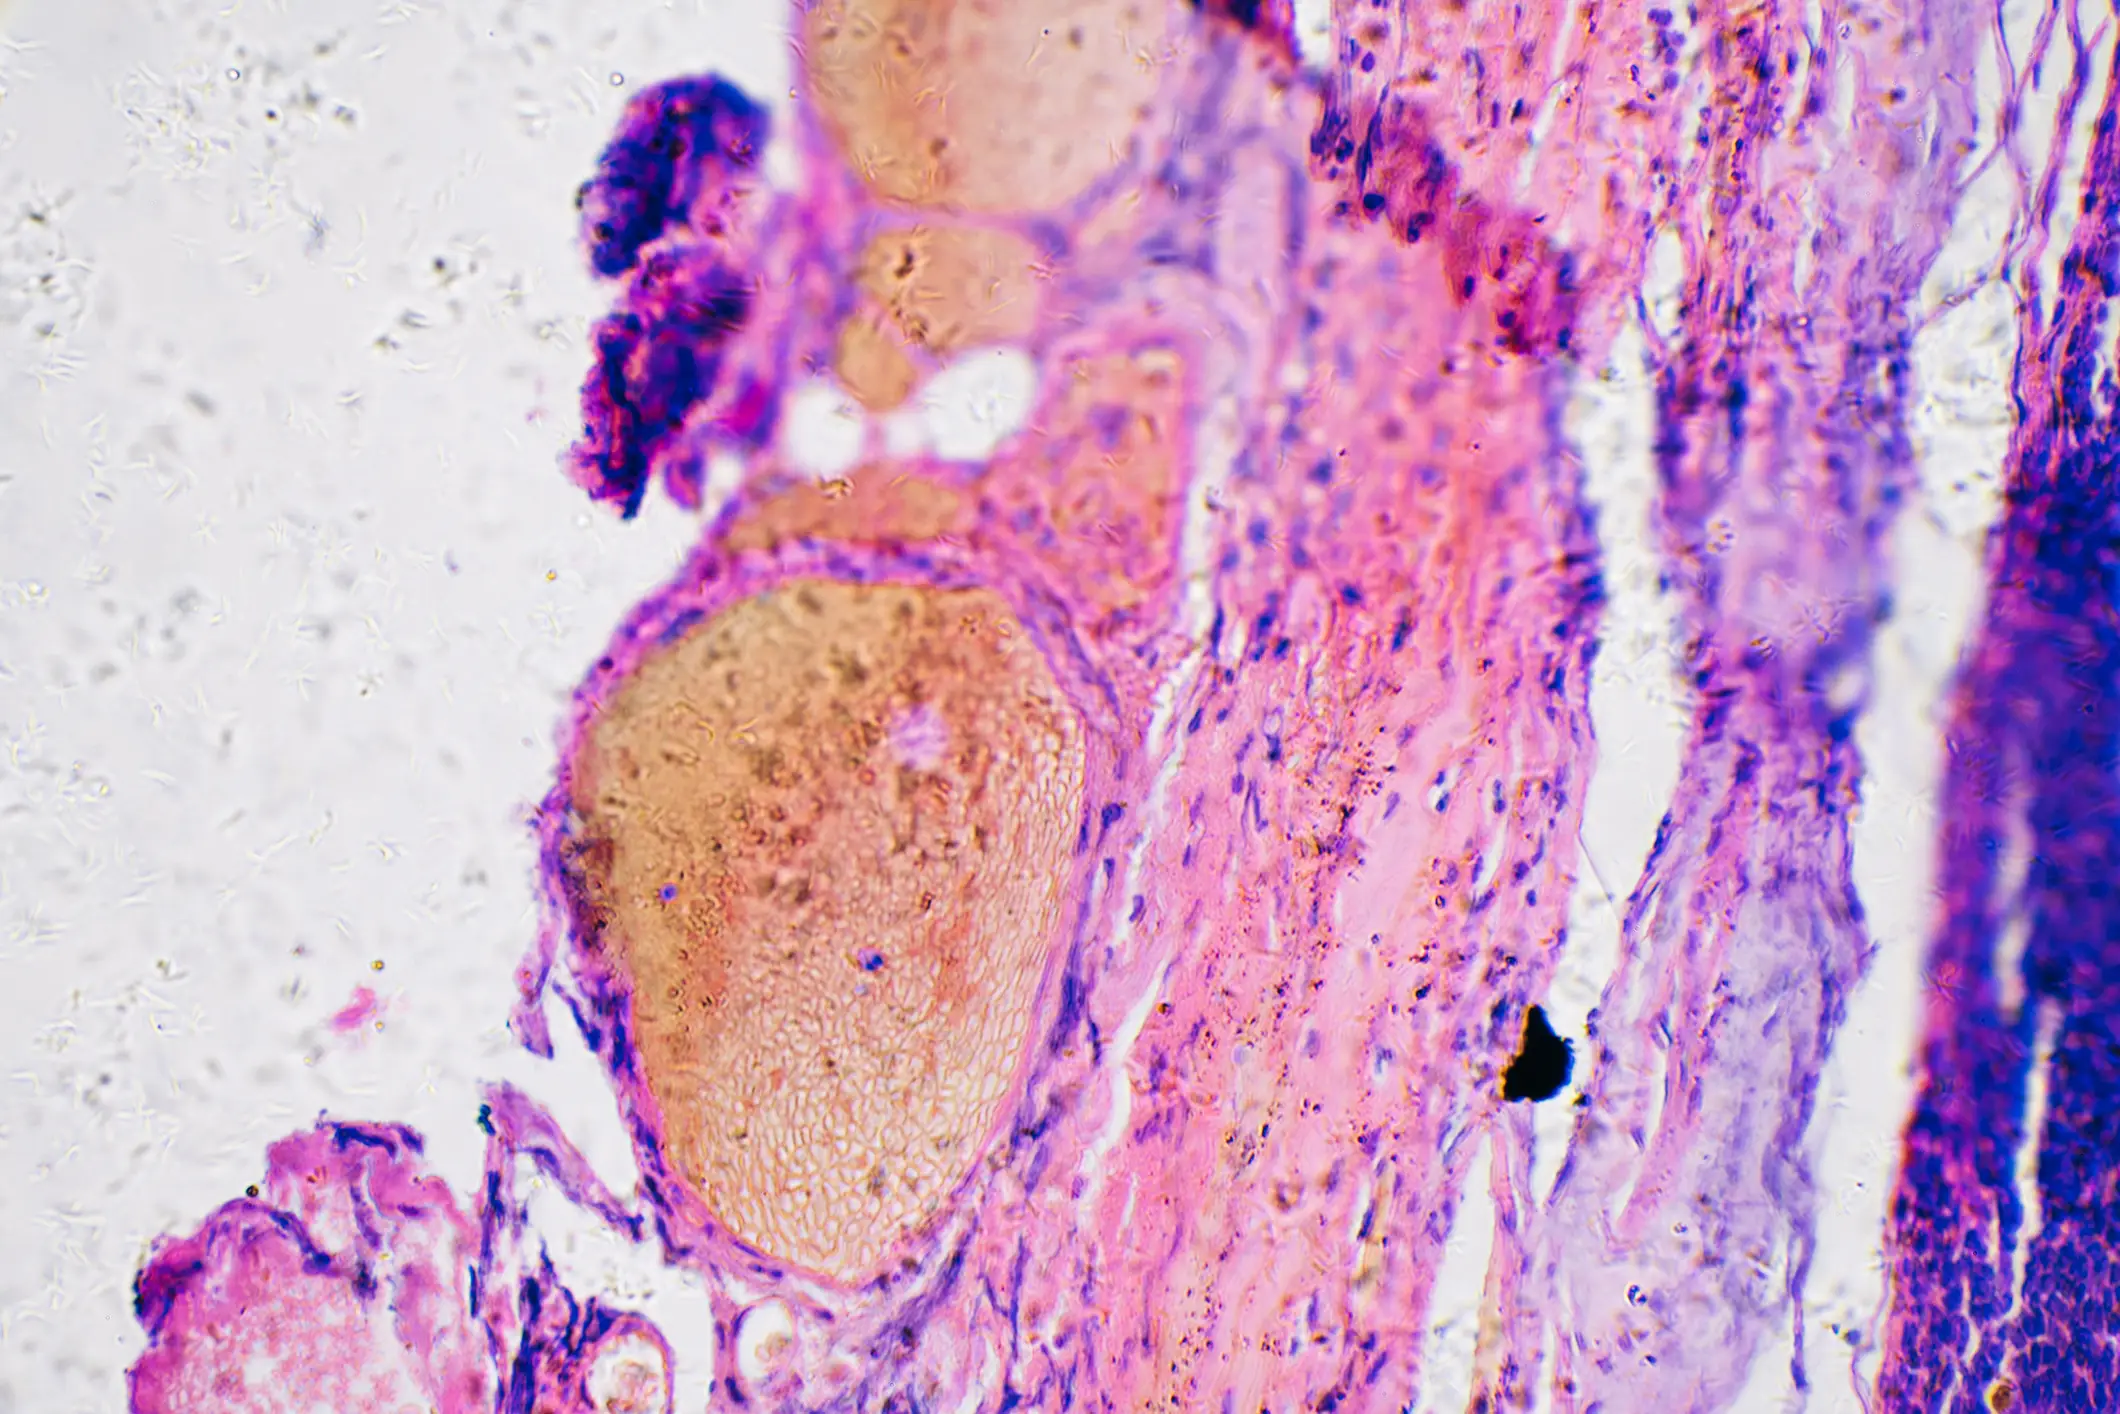

Further tests determined that the cyst was in fact melanoma, which is a form of skin cancer.

The American Cancer Society explains that melanoma is a type of skin cancer that develops when melanocytes grow out of control.

It is less common than some other types of skin cancer but it's more dangerous as it's more likely to spread if not treated.